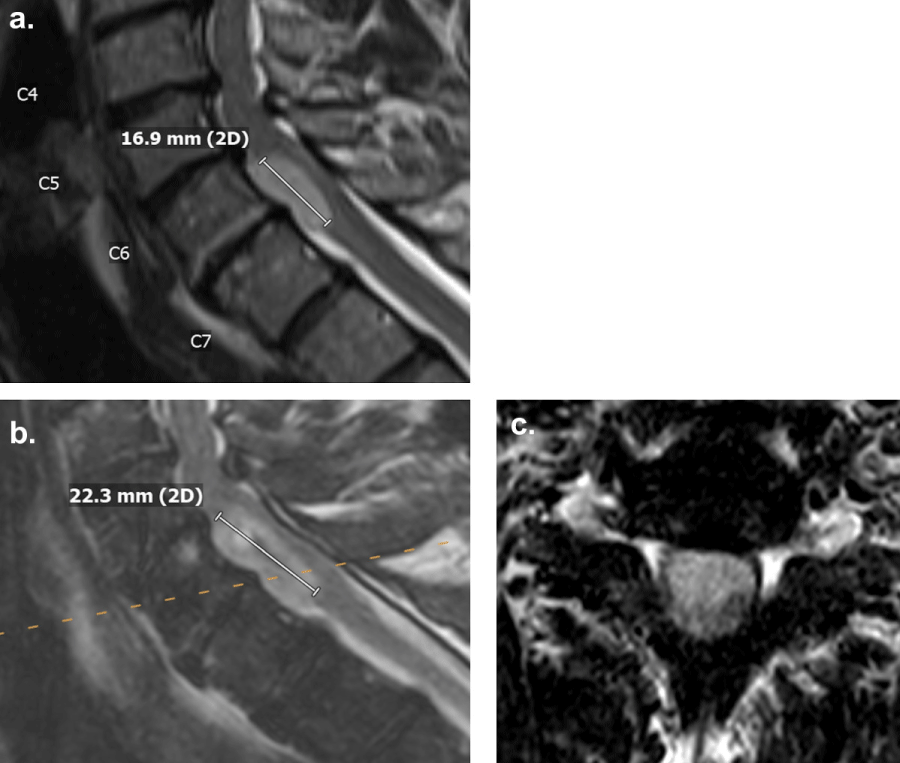

At the age of 56, the patient presented with radicular pain radiating from the left buttock down the left lateral thigh, as well as numbness and tingling in the left posterior thigh, after a fall three months prior. The physical examination demonstrated full strength in bilateral upper and lower extremities. Reflexes were unremarkable. A magnetic resonance imaging (MRI) with and without gadolinium contrast of the entire neuraxis, including brain, cervical, thoracic, and lumbar spines, as well as a computed tomography (CT) with contrast of the chest, abdomen, and pelvis, was ordered to evaluate for metastatic disease. MRI of the brain demonstrated a questionable enhancement in the posterior fossa resection bed (Figure 1a). MRI of the cervical and lumbar spines demonstrated a non-enhancing 1.7 cm lesion anterior to the spinal cord at the C6-7 levels, a 1.6 cm enhancing lesion eccentric to the left in the thecal sac at the L4 level, and a 5.6 cm enhancing lesion in the thecal sac of the sacrum (Figure 1b and Figure 1c). These three intradural extramedullary lesions were suggestive of drop metastases from the patient’s prior ependymoma.

Figure 1: MRI with gadolinium contrast demonstrating. (a): The posterior fossa; (b): A non-enhancing lesion at the C6-7 level; (c): An enhancing lesion at the L4 level and an enhancing lesion in the sacral thecal sac. View Figure 1